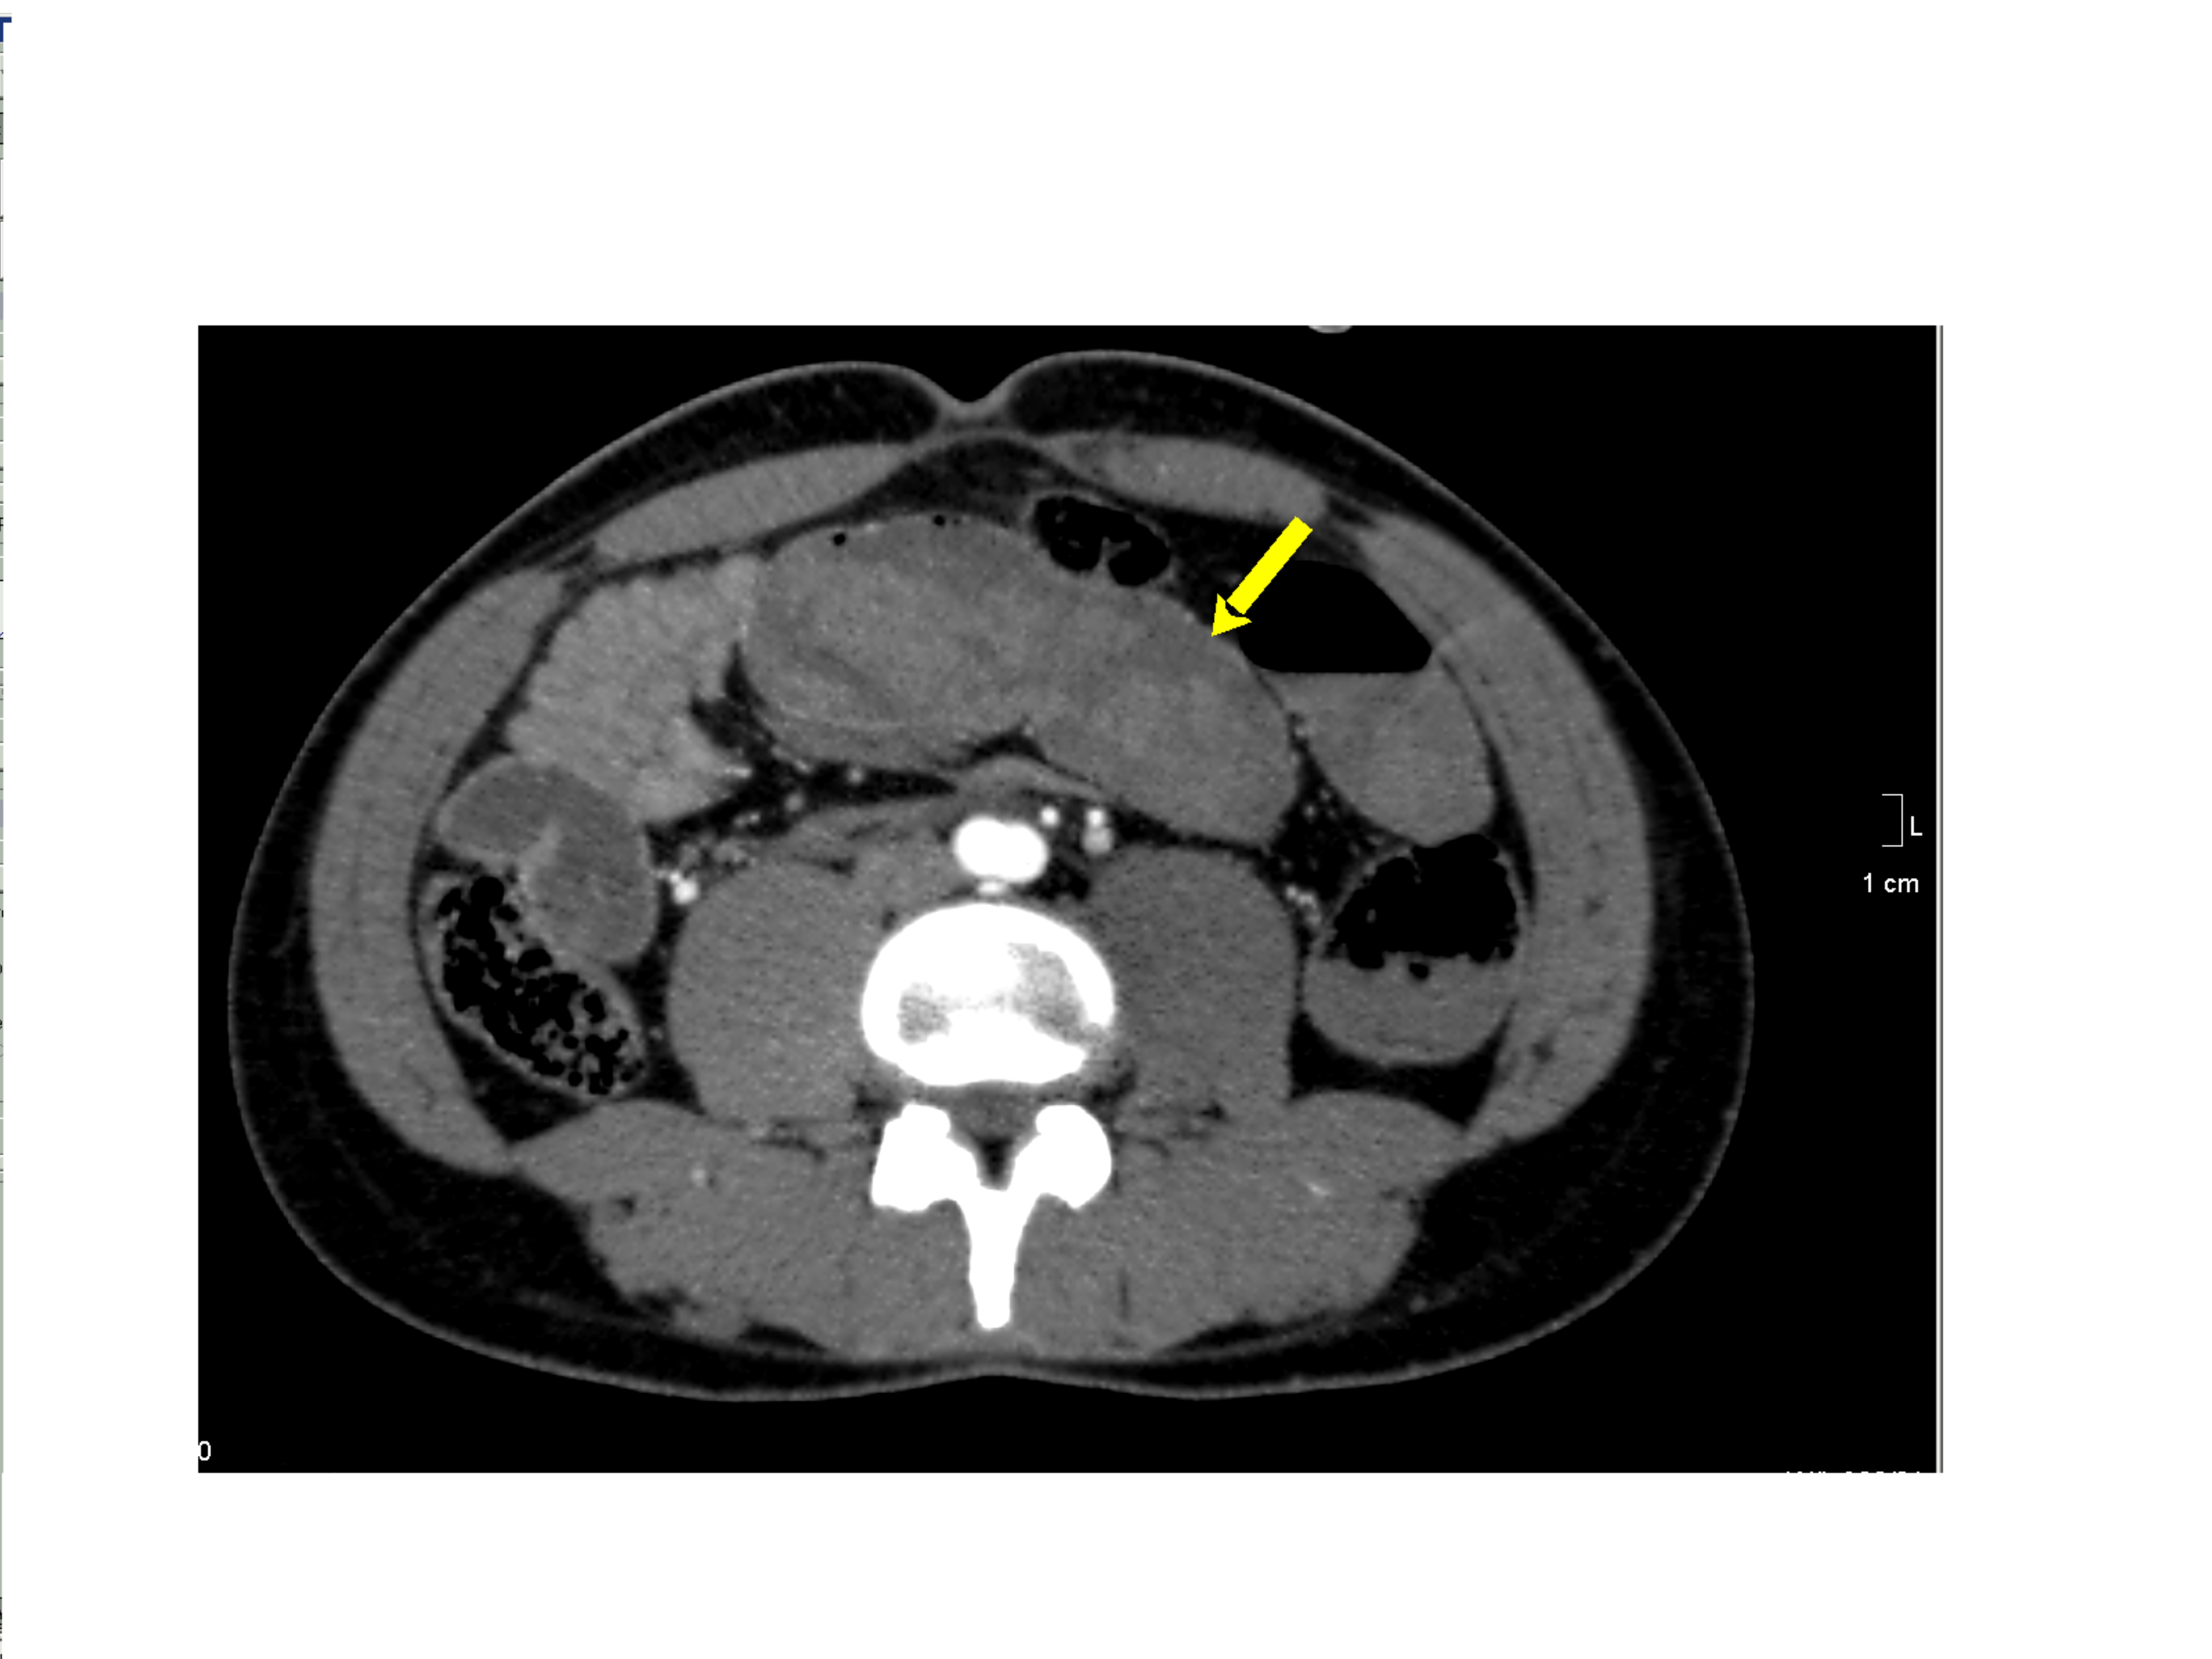

Small bowel obstruction is a common clinical presentation that presents a diagnostic conundrum. Over the last 2 decades, there has been a paradigm shift in the radiological investigation of small bowel obstruction (SBO) and in the indication for and timing of surgical intervention. Cross sectional imaging (predominantly computed tomography) has largely replaced the widespread use of radiographic small bowel follow-through studies as the imaging modality of choice for SBO. This article illustrates the current imaging modalities available for diagnosis of small bowel obstruction. (Full text available online at www.medpharm.tandfonline.com/ojfp) S Afr Fam Pract 2015; DOI: /10.1080/20786190.2014.977052